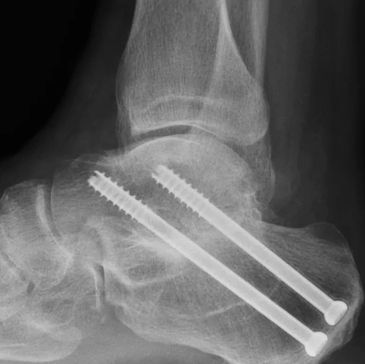

Calcaneus fixation surgery treats displaced heel bone fractures by restoring alignment and joint surfaces. It helps improve long-term function and walking ability after injury.